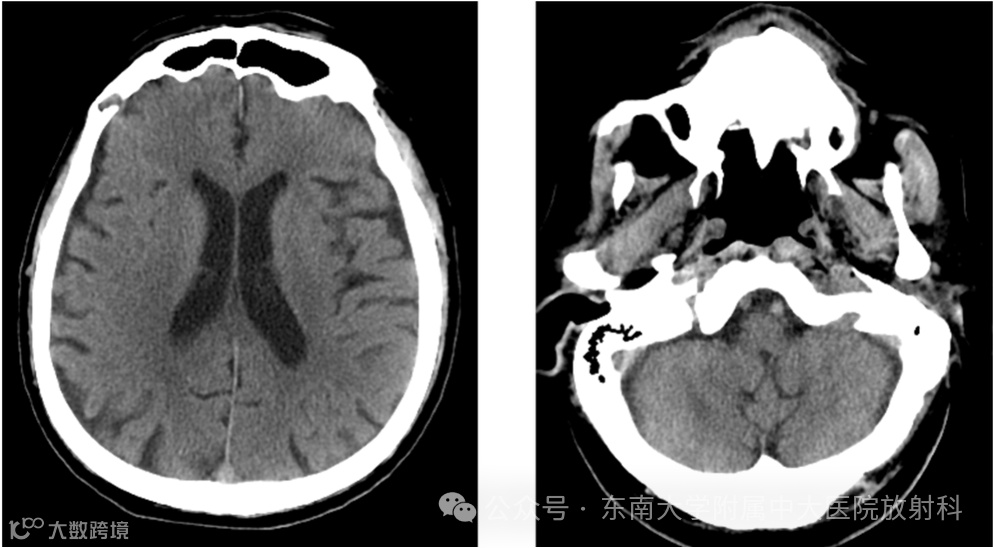

影像号:1217119452 2025-09-08 盆腔MR平扫